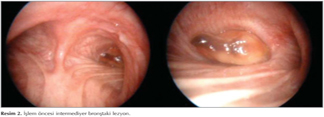

Yetmi? iki ya??nda, erkek hasta, May?s 2013 tarihinde sol yan a?r?s? ve hemoptizi ?ikayetiyle klini?imize ba?vurdu. Mevcut ?ikayetleri iki ay i?inde artan hastada d?? merkezde ?ekilen toraks ve abdomen tomografilerinde mediastinal lenfadenopatiler, sol akci?erde masif plevral ef?zyon i?inde ve parankimde multipl metastatik lezyonlar, sol b?brekte 126 mm nekrotik, egzofitik renal sinusa invazyon yapm?? malign kitle lezyonu ile sol surrenal lojda 24 mm'lik heterojen kitlesel lezyon saptand? (Resim 1). Hastan?n al?nan plevral s?v?s? malign sitolojiyle uyumlu olarak gelmi?. Hastaya sol b?brekten yap?lan tru-cut biyopsi sonucunda renal h?creli karsinom (?effaf h?creli tip ile uyumlu) saptanm??t?r. Hastaya yap?lan fiberoptik bronkoskopide sa? intermediyer bron?u tama yak?n t?kayan lezyon g?r?lmesi nedeniyle giri?imsel bronkoskopi yap?lmak ?zere hastanemize y?nlendirilmi?tir. Hastaya genel anestezi alt?nda rijid bronkoskop ile alt lob apikal segmentten kaynaklanan ve intermediyer bron?u tama yak?n t?kayan polipoid EBL 60 watt argon ile koag?le edilerek rijid forcepsle ??kar?ld? ve i?lem sonras? orta ve alt lob segmentlerinde tam a??kl?k sa?land? (Resim 2,3). Lezyondan al?nan biyopsi sonucu renal h?creli karsinom ile uyumlu olarak geldi (Resim 4).